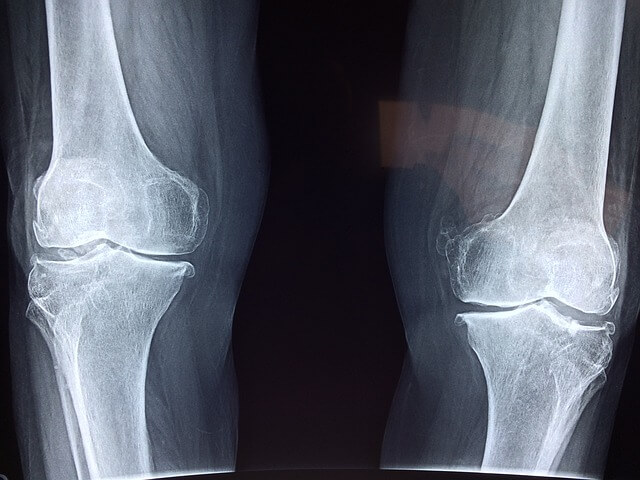

1) 퇴행성 관절염: 퇴행성 관절염은 나이가 들면서 발생하는 대표적인 무릎 통증의 원인입니다. 관절 내의 연골이 마모되면서 뼈끼리 맞닿아 염증이 생기고 통증을 유발합니다. 이로 인해 걷기, 앉기, 서기 등 기본적인 동작에 어려움을 느끼게 됩니다. 퇴행성 관절염은 보통 50대 이후에 발생하지만, 평소에 무리한 활동이나 비만이 있는 경우 더 이른 시기에 증상이 나타날 수 있습니다.

2) 연골 손상: 무릎의 연골은 충격을 흡수하는 역할을 합니다. 하지만 무리한 운동이나 사고로 인해 연골이 손상될 경우, 무릎 통증이 발생합니다. 특히 축구, 농구 등 격렬한 스포츠를 즐기는 사람들이 자주 겪는 문제입니다. 연골 손상은 통증뿐 아니라 무릎의 움직임에도 제한을 주기 때문에 조기 진단과 치료가 중요합니다.

3) 인대 손상: 무릎에는 여러 인대가 있어 무릎을 안정적으로 지지해 줍니다. 그러나 십자인대나 측부인대가 손상되면 무릎이 불안정해지고, 심한 경우 걷기조차 힘들 수 있습니다. 인대 손상은 주로 갑작스러운 방향 전환이나 충돌로 인해 발생하며, 특히 스포츠 활동 중 흔히 발생하는 부상입니다.

4) 슬개골 문제: 슬개골은 무릎 앞쪽에 위치한 작은 뼈로, 슬개골의 위치 이상이나 손상은 무릎 통증을 유발할 수 있습니다. 슬개골 연골연화증은 슬개골 뒤쪽 연골이 손상되는 질환으로, 주로 무릎을 많이 구부리거나 쪼그려 앉는 활동을 자주 할 경우 발생합니다.